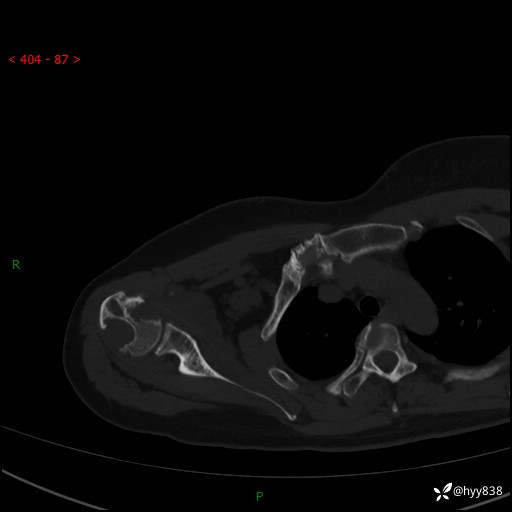

中年女性,发现右肩关节占位2天。有特征、有细节---结果公布~

年龄:47岁

主诉:发现右肩关节占位2天

现病史:患者3年前摔伤致右肩部疼痛,未行特殊处理,后右肩活动时轻度疼痛,患者未引起重视。1月前上述症状加重,于当地县人民医院就诊,2023-07-10右肩关节MR:右肱骨头、肩胛骨及周围软组织异常信号。现患者右肩可触及质硬包块,活动时疼痛,无头晕头痛、恶心呕吐、腹痛腹胀等,为求进一步治疗,来我科就诊,门诊以“右股骨占位性病变”收入我科。 起病以来,患者精神、饮食、睡眠可,大小便正常,体力、体重未见明显变化。

右肩关节CT平扫